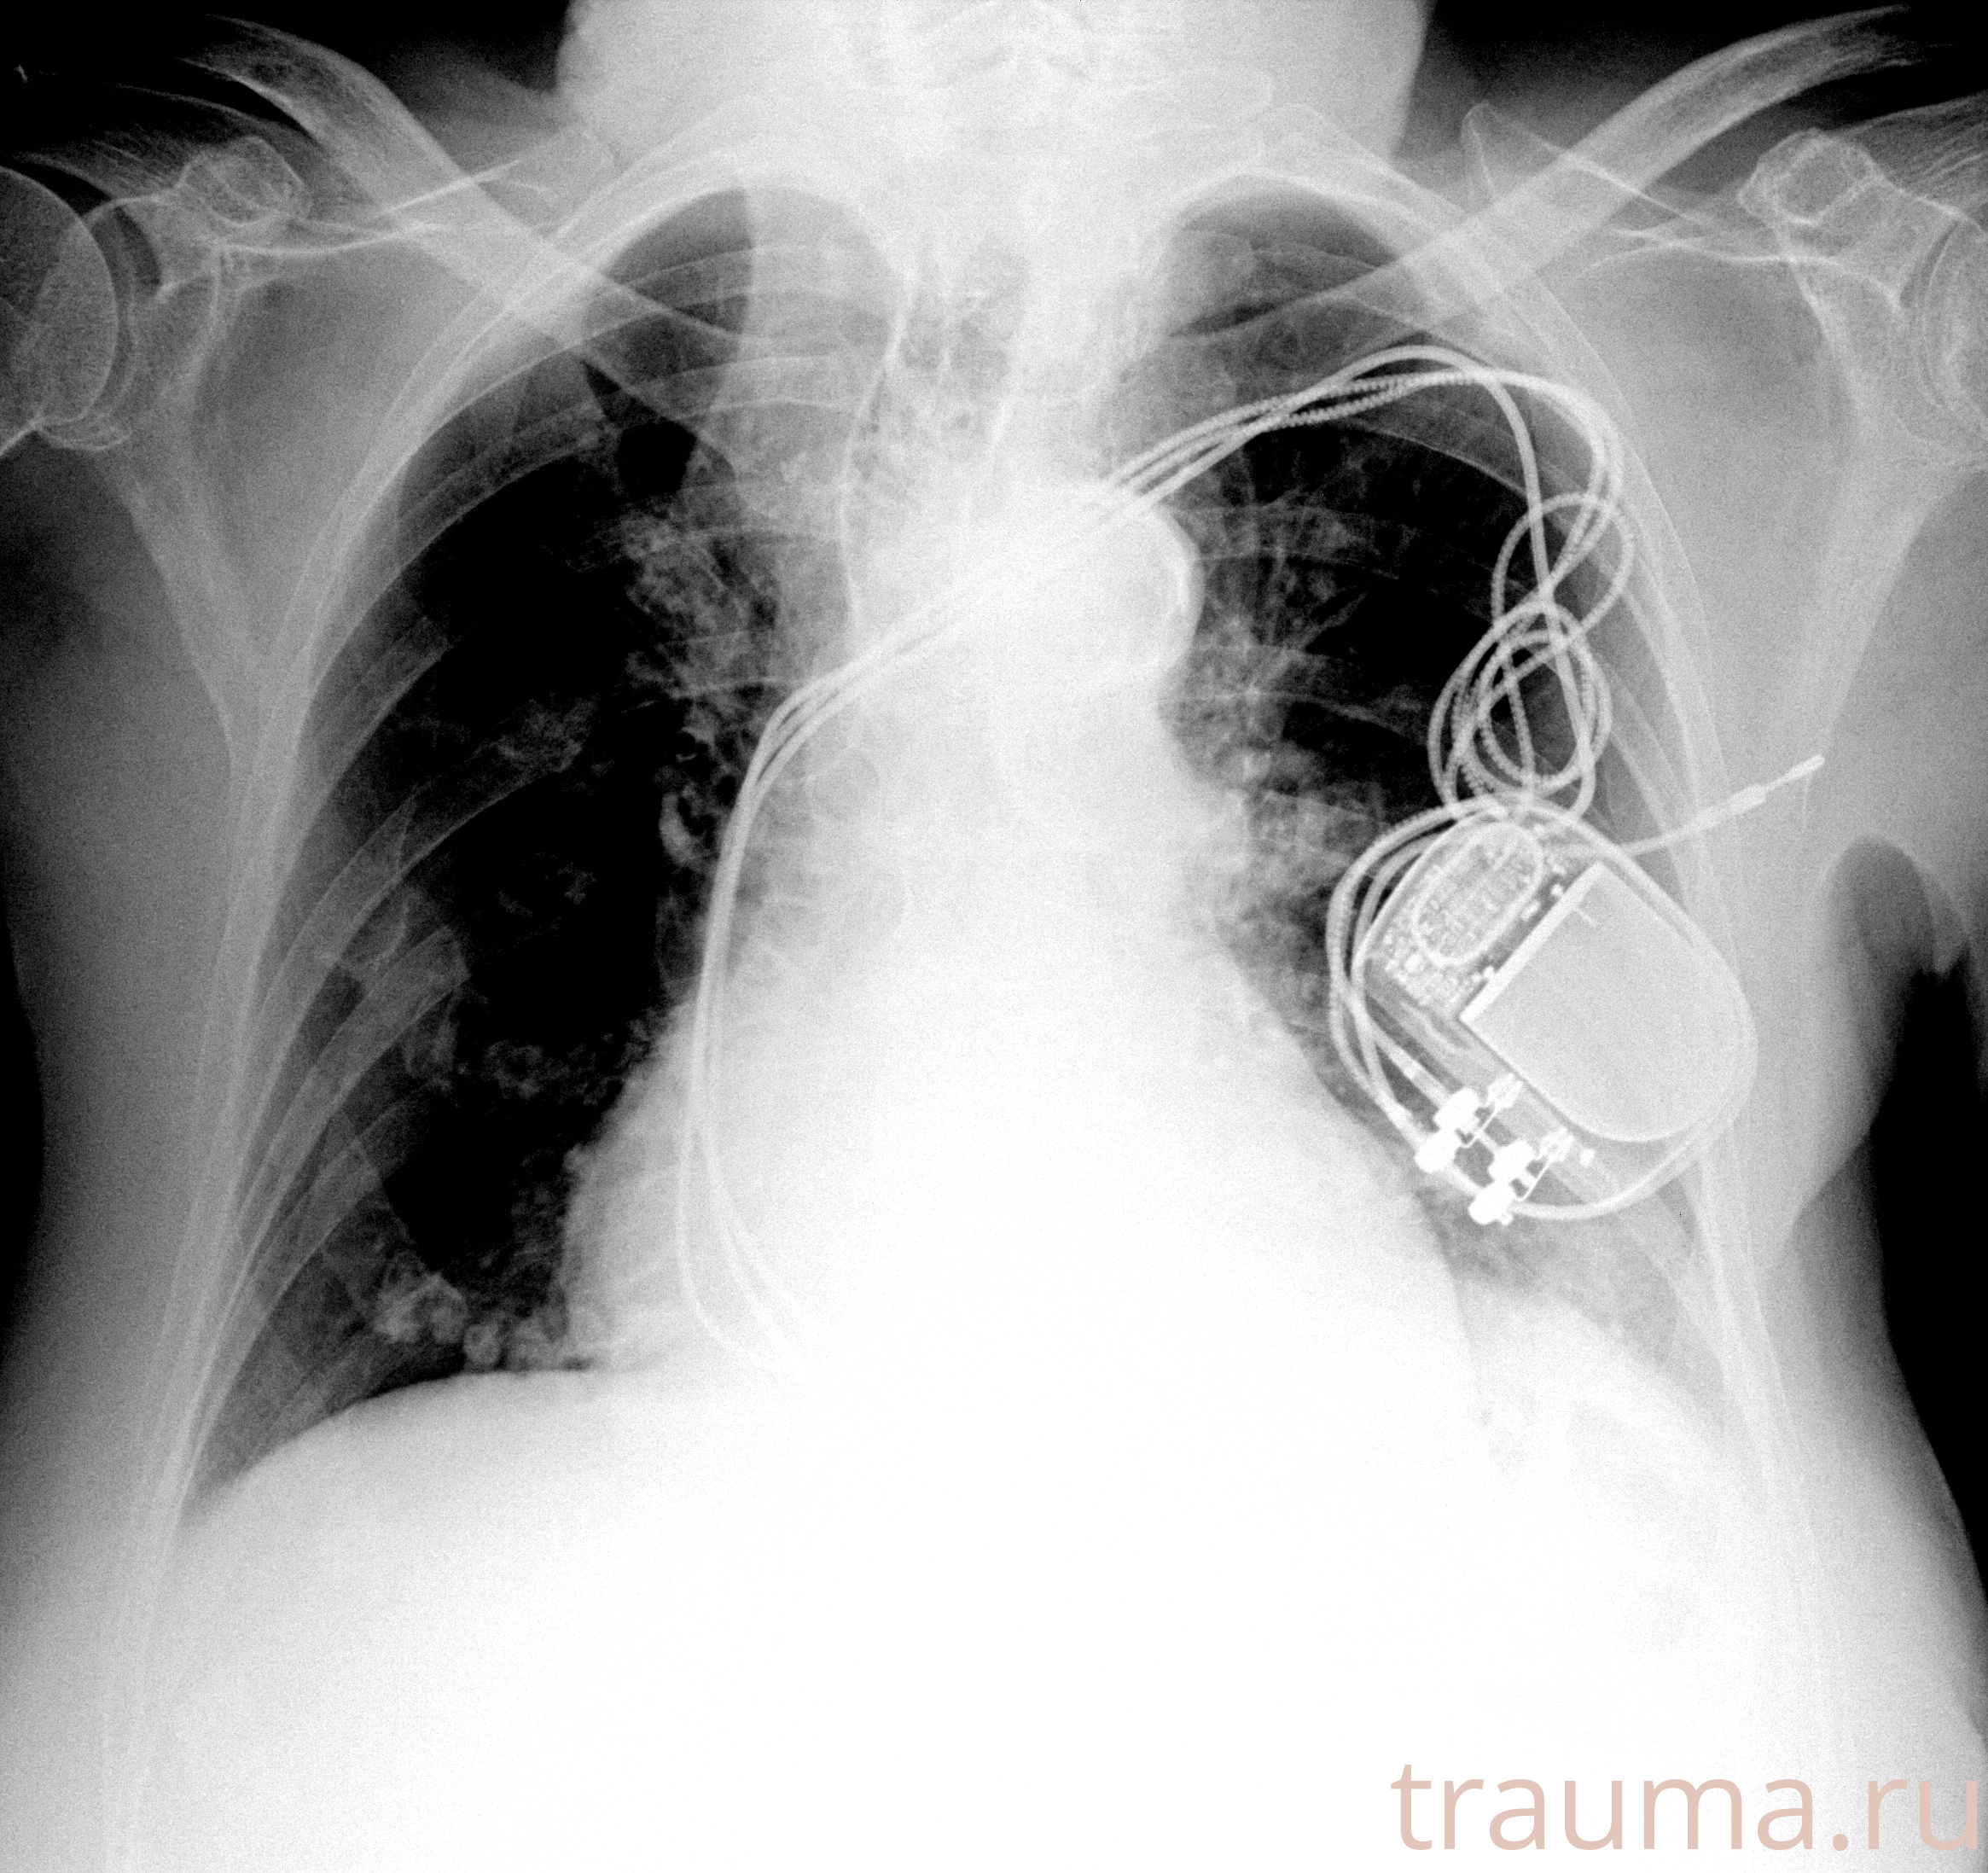

Рентгенограммы

Рентген на дому: по вашему адресу приезжает врач-рентгенолог, травматолог-ортопед с мобильным рентгеновским аппаратом, проводит диагностику травмы или заболевания, делает необходимые рентгенограммы, дает рекомендации по дальнейшему лечению. Получить качественные снимки в домашних условиях возможно благодаря уникальной методике, разработанной МосРентген Центром для института  Склифосовского